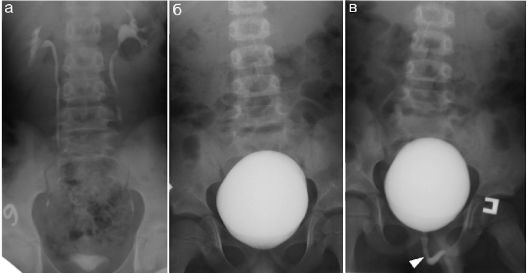

Медицинские изображения и примеры эксреторной цистографии